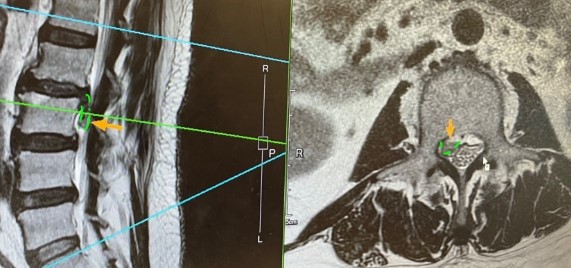

椎間盤突出壓迫神經示意圖

椎間盤突出壓迫神經根,造成腿部放射性疼痛(示意圖)